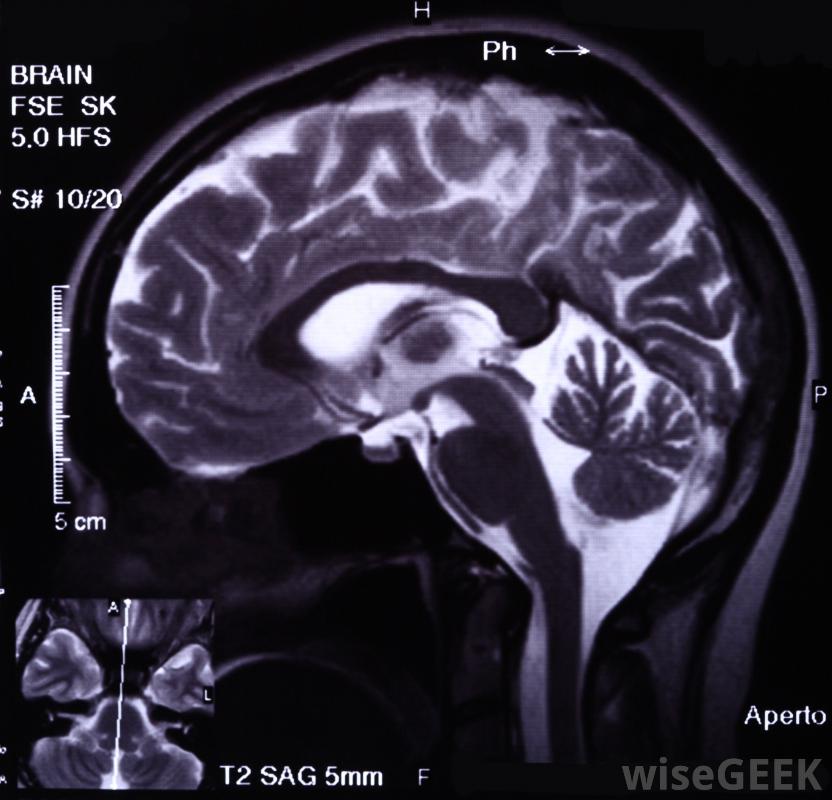

癲癇是一種慢性神經系統疾病,由于大腦中神經元活動異常,會影響大腦中負責記憶的區域。當癲癇發作發生時,與記錄記憶的大腦區域相連的神經遞質就會中斷。之后,短時記憶喪失癲癇發作是很常見的-患者可能不記得他們在哪里或他們在做什么;有時,完全健忘癥可能會持續長達一個小時。最終,反復發作的癲癇會對大腦的記憶區域造成損害,并導致永久性的記憶喪失。癲癇對記憶的影響會影響這兩個區域癲癇對記憶的長期影響也會導致語言和語言的困難。癲癇對記憶的長期影響也會導致語言和語言的困難。癲癇對記憶的影響有很好的記錄,那些患有這種疾病的人比那些患有其他神經系統疾病的人更容易出現記憶喪失問題。嚴重的腦損傷可能是癲癇發作的原因和后果。大腦記錄記憶通過一種被稱為編碼的過程,信息被分為兩類,短時記憶(STM)只會回憶幾分鐘的信息,長時記憶(long-term memory,LTM)能長時間儲存信息,大腦需要不斷的監測才能使記憶正常工作,癲癇發作的發生會導致這一過程的中斷癲癇發作后的短期記憶喪失是很常見的。記憶喪失幾乎總是發生在癲癇事件中,但是它的程度因人而異。那些患有嚴重癲癇的人通常報告說對這一事件沒有記憶。其他人會經歷一種被稱為順行性遺忘癥的情況,即大腦失去處理新信息的能力。這種情況通常會隨著時間的推移而自行解決。發作性失憶癥描述的是一個人在癲癇發作期間與周圍環境正常互動,但對他們之間的相互作用沒有記憶。大腦癲癇可能是由于長期服用藥物引起的長期來看,癲癇發作會對大腦造成永久性損害。癲癇通常會影響大腦的特定區域,反復發作通常會對腦組織造成損害,由于癲癇患者大腦中持續的異常電活動,癲癇發作之間也會發生損傷。某些類型的癲癇發作可能會導致持續性發作腦損傷由于大腦的不同區域受到傷害,可能會出現不同類型的記憶喪失。一個右側大腦受到影響的人可能會出現視覺記憶問題,而左側大腦受損會影響言語記憶,從而導致書寫和言語受限。癲癇襲擊額葉通常會導致無法集中注意力。癲癇的治療方法還不清楚,有幾種治療方法可以限制癲癇對記憶的影響。醫生通常會開抗驚厥藥來控制或完全消除癲癇發作,從而保留大腦功能和記憶。在極端情況下,當藥物對阻止癲癇發作復發作用不大時,可能需要動手術患有癲癇對記憶有影響的人通常也會尋求記憶訓練。一般來說,記憶改善是不可能的,但是使用記憶法和其他記憶輔助手段的訓練可以改善日常生活。訓練必須是單獨設計和專門的,以治療癲癇對記憶的特殊影響。醫生可以使用腦電圖來確診為癲癇。